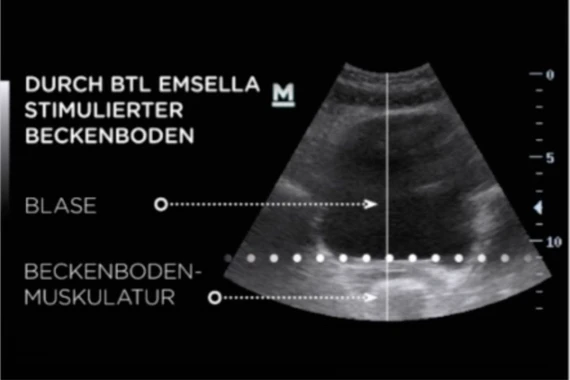

Ultraschall-Vergleich: Vorher und Nachher

Ultraschallbild: Durch BTL EMSELLA® stimulierter und gestärkter Beckenboden

Nach der Behandlung